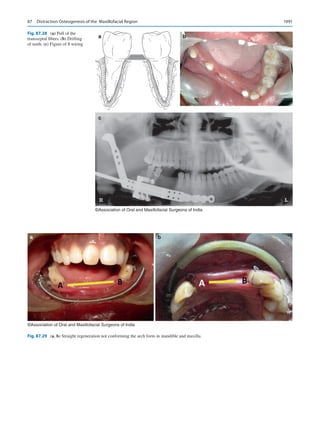

for empires, so for OMS. Our mistakes and pettiness must be

acknowledged, accounted for, and learned so as not to repeat

them.

We might have the ability as a specialty to control most of

our destiny, but some of it may be adapted based on our envi-

ronments. At the end of it all, if the specialty takes heed of